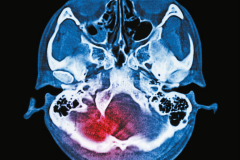

W Neurologii prezentujemy przegląd metod rehabilitacji stosowanych przy urazowych uszkodzeniach mózgu, skupiający się na ich skuteczności. Publikujemy też tekst o wpływie wymagającego treningu równowagi na sprawność pacjentów z parkinsonem, zwłaszcza na prędkość chodu, która jest istotnym wskaźnikiem stanu zdrowia wszystkich osób starszych.